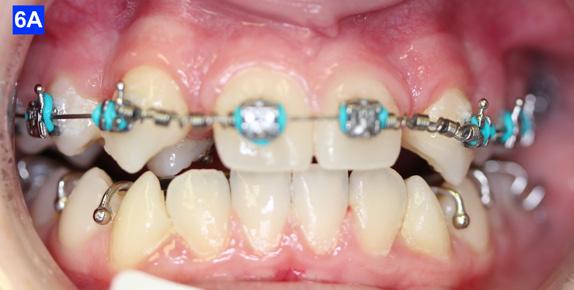

When the maxillary teeth were leveled, we placed a .018 SS arch wire and an OCS to create as much space as possible for the lateral incisors. This technique also allowed us to increase the inclination (torque) of the central incisors as they were too retrusive at the start of the treatment (U1/SN 91°). The maxillary lateral incisors were now completely retracted (Figure 6-A, B).

Figure 5A: Adrian “U” bend spring, frontal view Figure 5B: Adrian “U” bend spring, right lateral view Figure 5C: Adrian “U” bend spring, left lateral view Figure 5D: Continuation of retraction, occlusal view Figure 6A: OCS between the central incisors an the cuspids Figure 6B: Retraction of the lateral incisors is completed Figure 7A: Starting treatment on the mandibular arch, frontal view